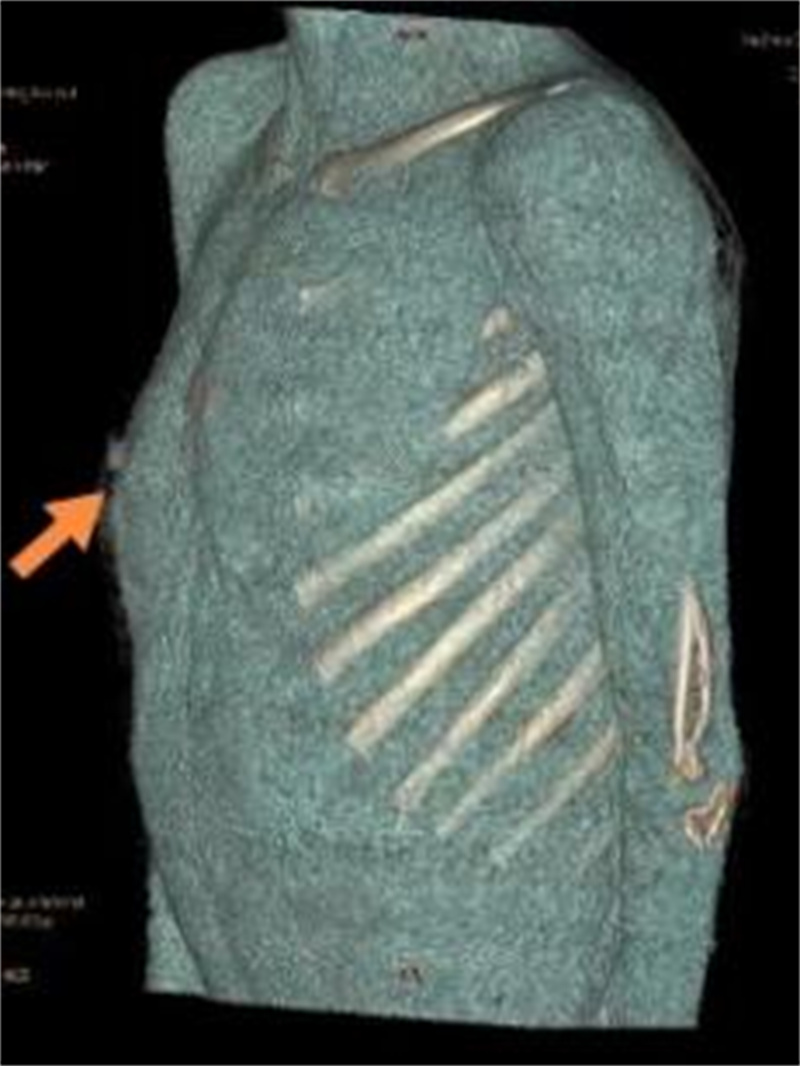

徐州市儿童医院科普:关注儿童及青少年胸壁隆起 叉状肋